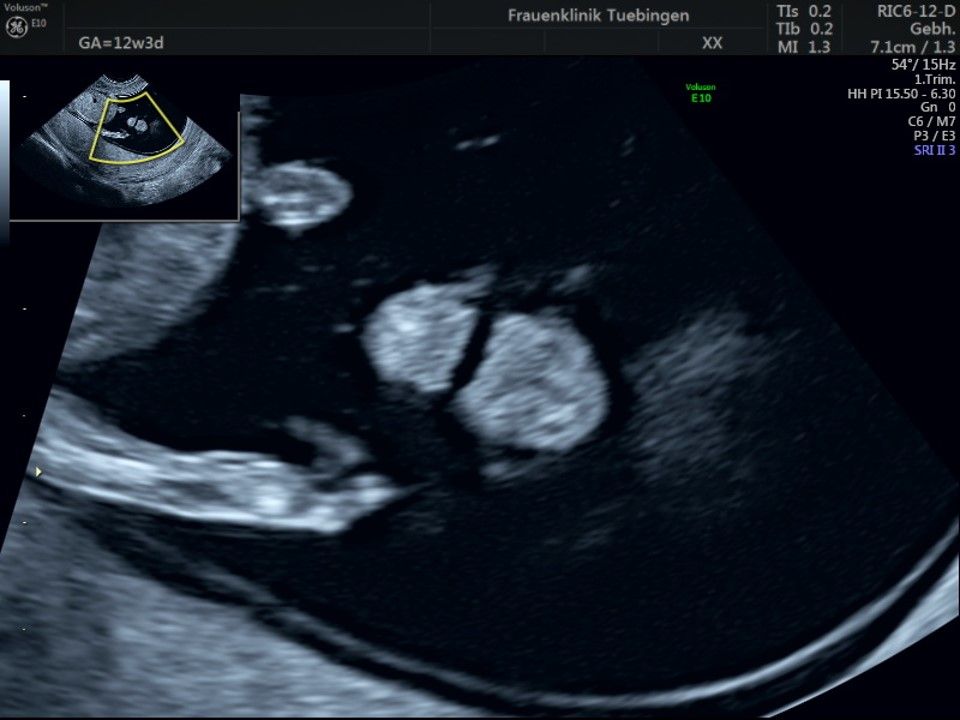

Im Rahmen des Ersttrimester-Screenings untersuchen wir die Organe des Feten mittels Ultraschall. Dabei machen wir auch gerne ein Bild für Sie.

Obwohl der Fet zu diesem Zeitpunkt erst zwischen 5 und 8cm groß ist, lassen sich bereits etwa die Hälfte aller schwerwiegenden Fehlbildungen erkennen bzw. ausschließen. Sollten wir eine Auffälligkeit sehen, werden wir mit Ihnen den Befund und das weitere Vorgehen ausführlich besprechen.

Fetale Anatomie

Herz

Bauchwanddefekt